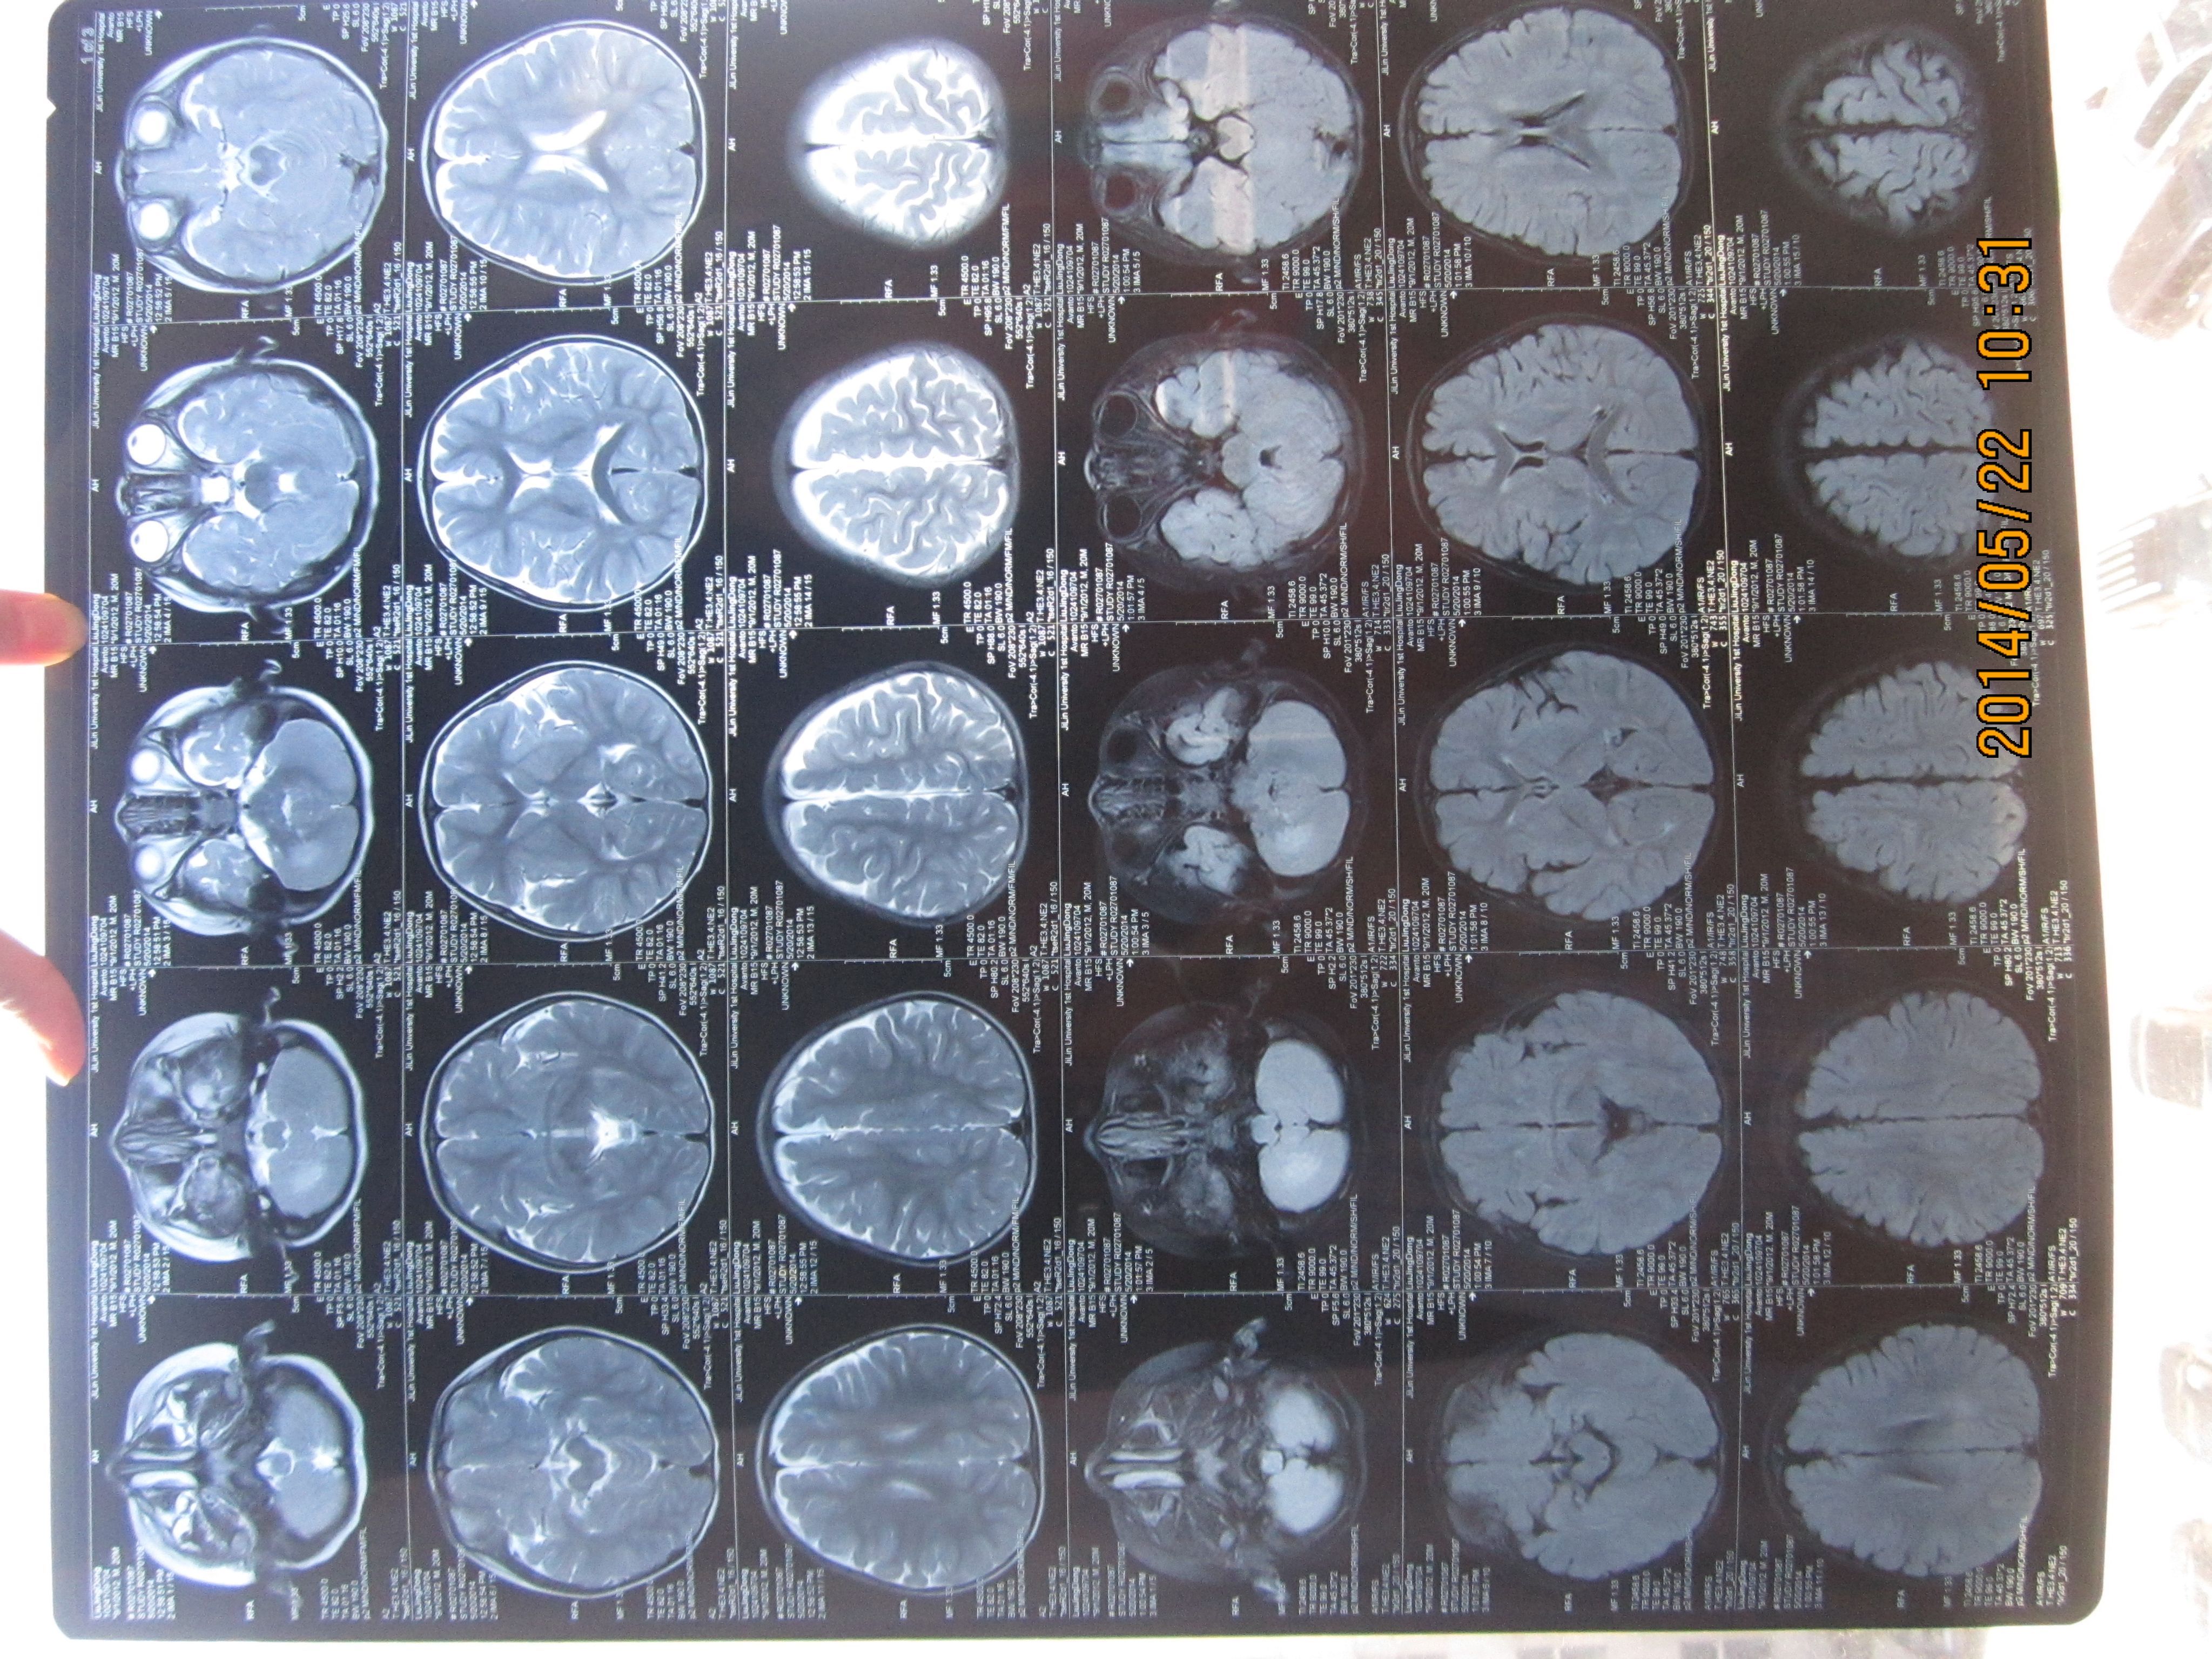

孩子8个月时做了核磁,医生说是小脑血管瘤 20个月时,小孩晚上睡了一觉醒来,右脚没劲,不能行走(孩 子一直走路不好,但也能走3米左右),做完核磁,医生诊断为突发性小脑炎。距发现孩子不能走三天后,孩子的脚慢慢恢复了正常,期间未做任何治疗。想知道孩子究竟小脑里怎么了,是什么病,上哪儿能治疗? 点击展开 匿名用户 2014-05-22 11:07 为您推荐: 其他回答 病情分析: 您的情况考虑是血管瘤, 指导意见: 一般来说是良性,生长缓慢,很少恶变。可用冷冻疗法或手术切除,也可用X线照射治疗。 种凌丝_IyuJ 2014-05-22 12:04 相关问题 小孩下肢痛,彩超,及核磁显示,血管畸形,说是血管瘤,问有什么好的治疗方法吗? 核磁能诊断肝血管瘤还是肝癌吗,1CM大小 核磁发现腰1椎体血管瘤,骶2有个囊肿